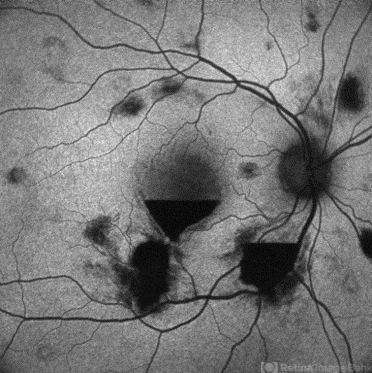

- subhyaloid hemorrhage, preretinal hemorrhage, anaemic retinopathy

- AUTOFLUORESCENCE IMAGE OF A 23 YEAR OLD MALE WITH SUBHYALOID HEMORRHAGE IN A CASE OF ANAEMIC RETINOPATHY